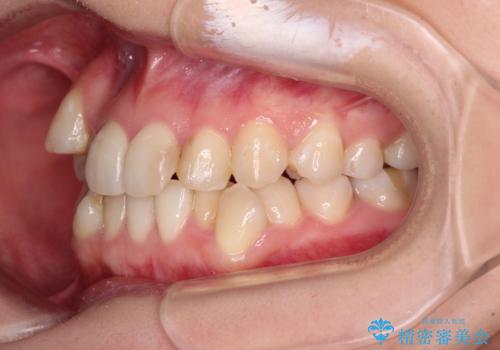

八重歯のためずれていた上下の正中をほぼ一致する位置に整えることができました。

重なって汚れの溜まりやすかった部分も改善され、大変満足していただけました。